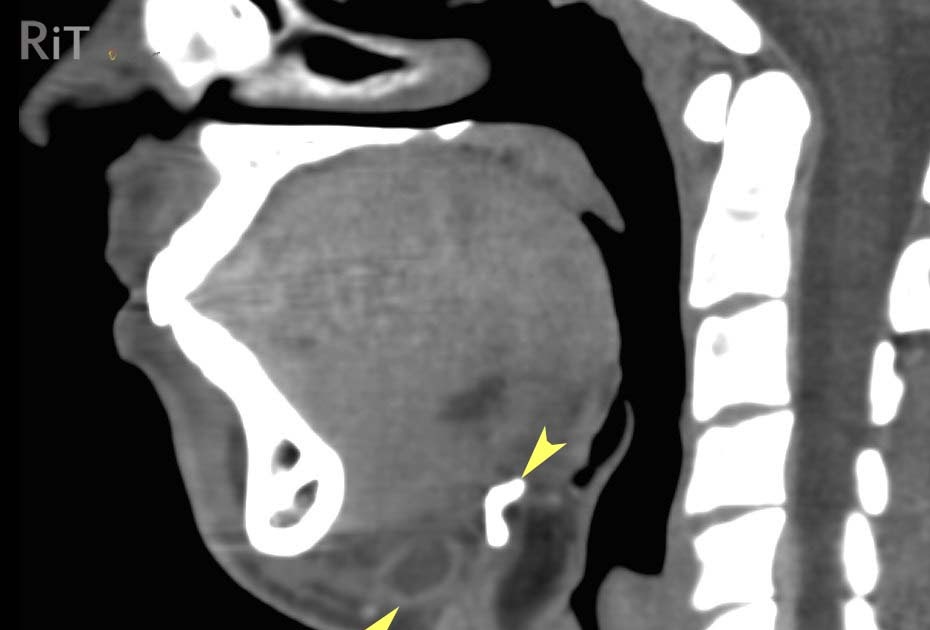

From radiologyinthai.blogspot.ca

RiT radiology Thyroglossal Duct Cyst Hyoid Bone Cyst Removal the procedure involves excision of the cyst, central portion of the hyoid bone, and the tract up to the foramen cecum. in 1920 dr walter ellis sistrunk described the classic operation of thyroglossal cyst excision; However, recurrence is a known possible outcome. surgical removal is the definitive treatment; The sistrunk procedure takes about 90 minutes and. . Hyoid Bone Cyst Removal.